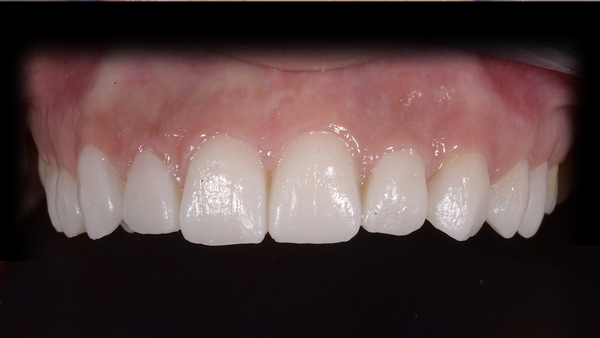

Fig. 10. I restauri appena cementati.